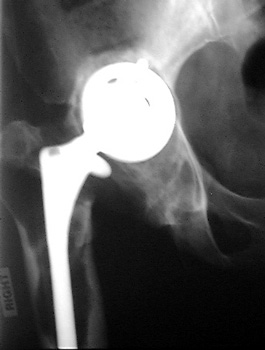

INFECTION Progressive interface widening about acetabular component